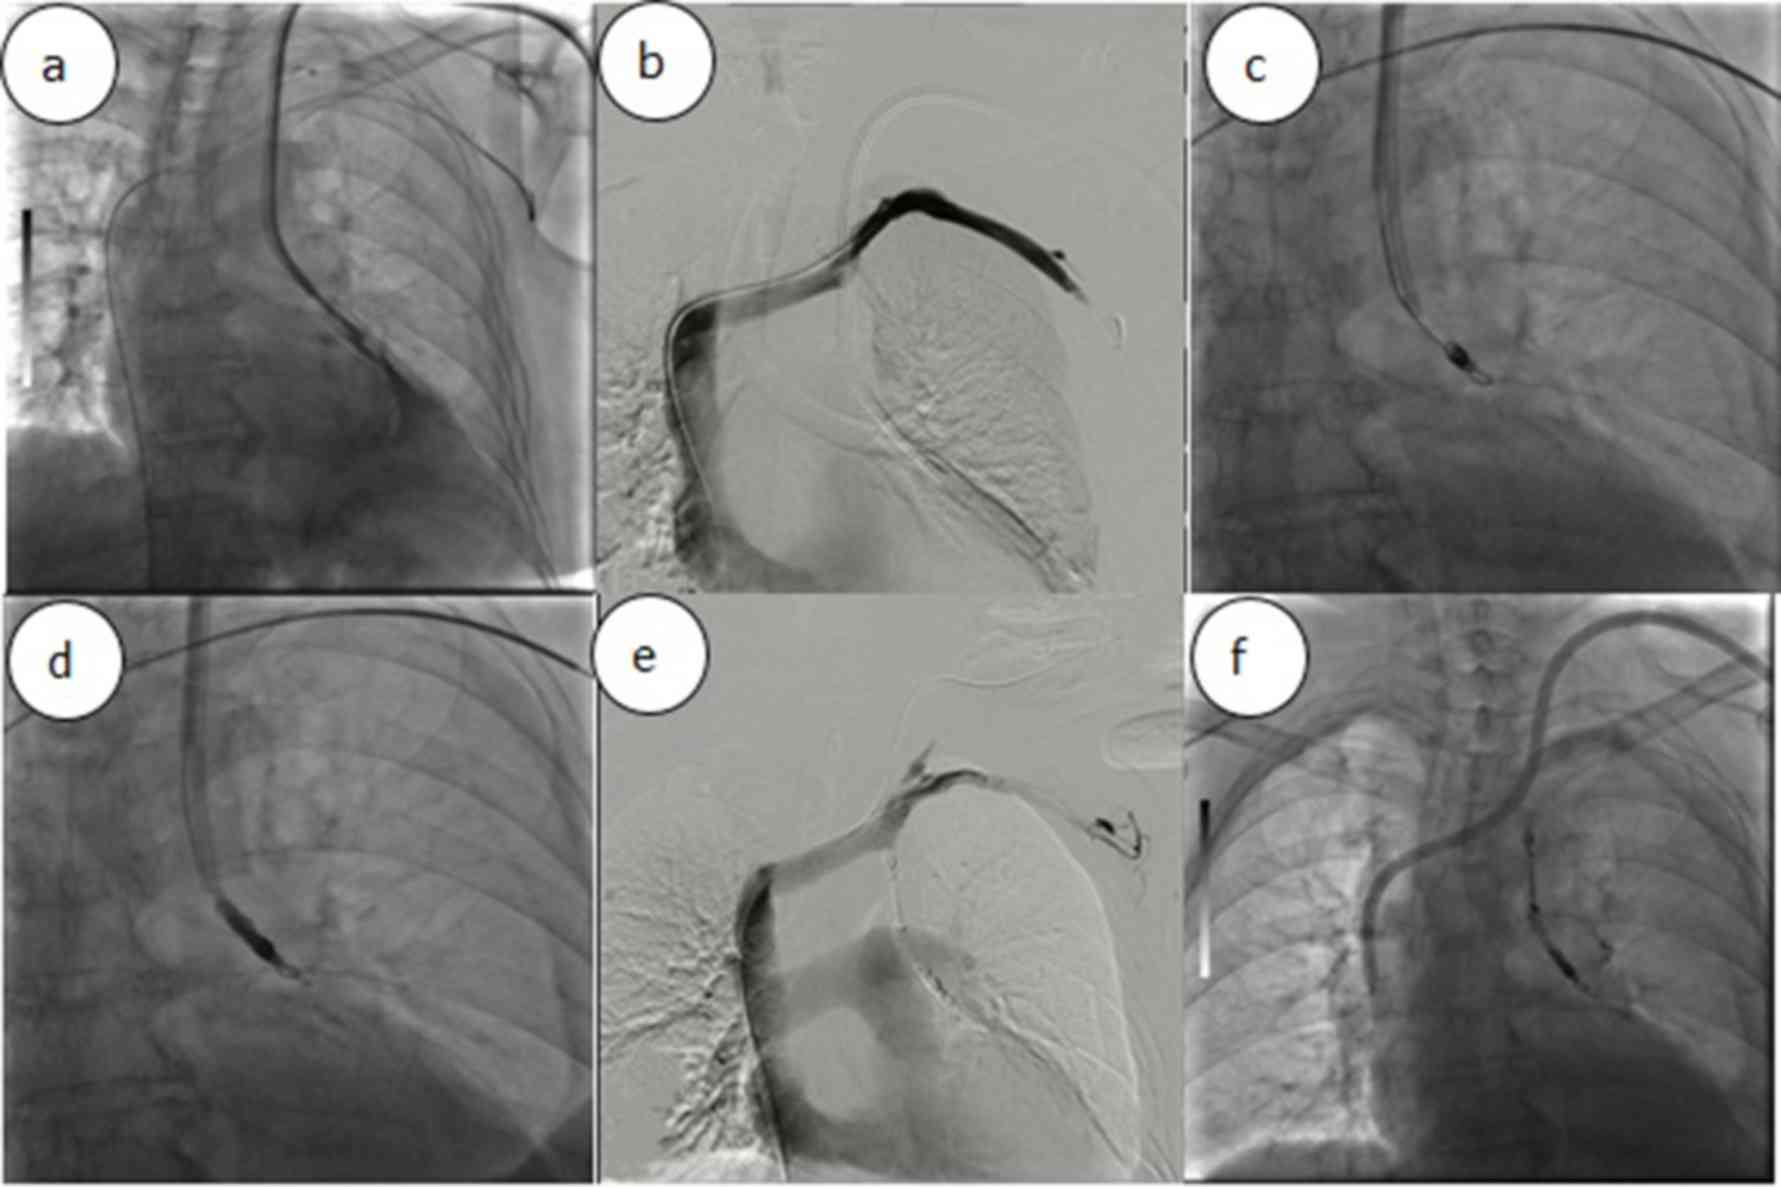

The present study reported a case of left BCV perforation that was diagnosed at the First Affiliated Hospital of the University of Science and Technology of China (USTC; Hefei, China). The present study was approved by the Ethics Committee of The First Affiliated Hospital of the USTC and informed consent was also obtained from the patient. A 64-year-old female with a 15-year history of hypertension underwent left forearm arteriovenous fistula (AVF) surgery to treat stage-V chronic kidney disease (CKD) five years previously. One month prior to presentation at our department on June 8, 2017, the patient had a fistula obstruction and a local hospital placed a temporary catheter in the patient's right femoral vein for hemodialysis. However, the inserted catheter caused occlusion of the right BCV. Review of the patient's medical history revealed that she received a long-term hemodialysis catheter (hemosplit 14.5F/23 cm; BARD) via the left internal jugular vein (LIJV) two days prior to occurrence of HS. LIJV punctures using the Seldinger technique were performed under local anesthesia, followed by smooth introduction and positioning of the guidewires in the left IJV to a level just below the diaphragm. After dilator and guidewire removal, the catheters were introduced, followed by removal of the peel-away sheaths. When placing the catheters, the surgeon felt a marked resistance. Furthermore, the patient reported mild pain and discomfort in the left chest during the catheterization process. After the completion of catheterization, hard venous blood was aspirated. The surgeon considered the possibility of acute thrombosis. A total of 200,000 units of urokinase were injected into the catheter, revealing obstructed flow after 20 min. Subsequently, the patient developed symptoms of palpitations, chest stuffiness and cold sweats. Thoracic anteroposterior radiography at the emergency department indicated that the body segment of the dialysis catheter was located on the left side of the mediastinum (Fig. 1). Therefore, the patient was rapidly transferred to our hospital. Upon admission, general and systemic examinations were unremarkable except for pectoralgia on the left side and chest tightness accompanied by asthma or breathing difficulties/obstruction, an elevated heart rate (115 beats/min) and hypotension (blood pressure, 82/45 mmHg). Laboratory investigations revealed a red blood cell count of 1.72×1012/l (normal range: 3.5~5.5×1012/l) and a hemoglobin level of 59 g/l (normal range: 110–150 g/l). A contrast-enhanced chest computed tomography scan revealed that the left BCV was perforated through the mediastinum and entered the left thoracic cavity, with the appearance of pleural effusion (Fig. 2a-d). A pleural puncture was performed to extract nonclotting blood. According to the above symptoms, the patient was diagnosed with central venous perforation and HS. The patient immediately received anti-shock treatment by fluid infusion and blood transfusion. The patient was given 6 U total transfused red blood cells and 800 ml fresh frozen plasma. Subsequently, the patient's blood pressure rose to 90–100/50–60 mmHg and the heart rate was reduced to 100–110 beats/min. However, there were obvious symptoms of pectoralgia, which was aggravated when breathing and coughing. Since the patient had evidence of a bleeding disorder with unstable vital signs, it was decided to perform intracavitary treatment to repair the damaged blood vessels. A total of 10 µl non-ionic contrast medium (Iodixanol; 27 g/100 ml; Amersham Health) was injected into the dialysis catheter, and X-ray fluoroscopy indicated that the contrast agent entered the left thoracic cavity through the front of the dialysis catheter and quickly dispersed (Fig. 3).

Figure 3.

(a) Chest X-ray revealing that the contrast agent entered the left thoracic cavity through the front of the dialysis catheter and dispersed quickly. (b) Left subclavian venography indicating steady blood flow. (c) Radiograph demonstrating catheter in sinus tract after deployment of angiographic coils; (d) Retrograde cholangiogram after application of N-butyl cyanoacrylate glue demonstrating the cessation of the contrast agent leak; (e) angiography demonstrating good sealing of the fistula after removing the dialysis catheter; (f) semipermanent dialysis tube placed in the superior vena cava.

A puncture needle was inserted into the left femoral vein, which was implanted with the 10F catheter sheath. Angiography revealed that steady blood flow was present in the left subclavian vein (LSV), cephalic vein and superior vena cava with no obvious leakage of the contrast agent. A guidewire (RFxPA35263M; 260 cm; Terumo Corp.) was left in the LSV to seal the sinus groove in the case of unsuccessful sinus embolization. A 4F catheter (Yashiro; Terumo Corp.) was inserted into the sinus canal through the artery end of the original dialysis catheter, followed by a 3F microcatheter (Progreat; Terumo Corp.). A total of four coils (6×50 mm, Fibered Platinum Coil; Boston Scientific) were then anchored at the fistula through the catheter. Cyanoacrylates [n-butyl-2-cyanoacrylate (NBCA)/n-octyl cyanoacrylate; Fuaile] were mixed with lipiodol (Guerbet) at a proportion of 1:2 and 1.5 ml was injected under fluoroscopic guidance. The long-term dialysis catheter was then replaced at the original puncture site under fluoroscopy and placed in the superior vena cava. Post-operative blood transfusion, fluid infusion and chest drainage were continued. The HGB level increased to 103 g/l on the third day after the operation, and the patient was discharged from the hospital. The patient was followed up with for one year and she did not experience any hemorrhage or central venous stenosis.